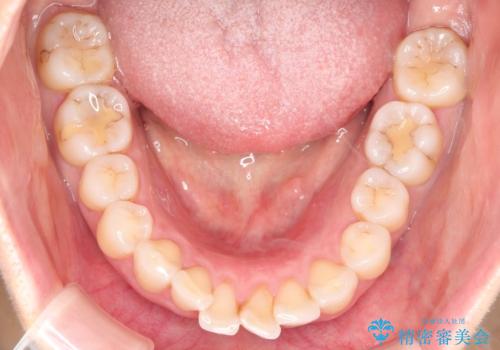

- 患者様は**歯の凸凹(叢生)**を気にされて来院されました。診査の結果、歯列のスペースが不足しているものの、抜歯をせずに改善できる状態でした。そこで、目立ちにくい審美装置(白いブラケットとホワイトワイヤー)を使用したワイヤー矯正を提案しました。歯列のアーチを広げながら、適宜IPR(歯の幅をわずかに調整する処置)を行い、非抜歯で自然な歯並びへと導く計画を立てました。